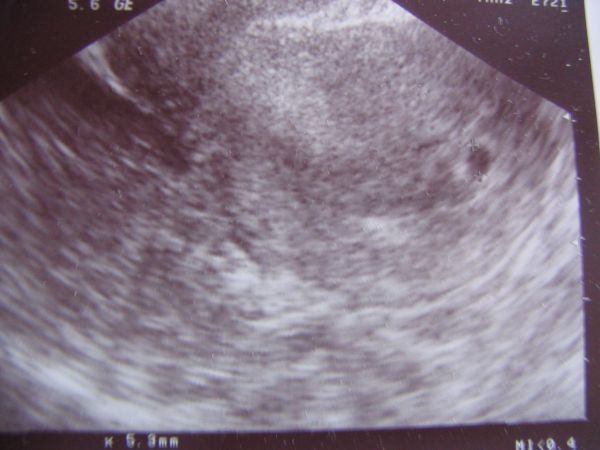

Megvizsgált és vaginális UH-t is végzett. A "diagnózis": Megnagyobodott uterus cavumában egy

9x5.6mm szabályos petezsák látható, fundusban jó helyen. Subcharialis haematomára utaló jel nincs. Embrio még nem ábrázolódik. Biometriai adatok alapján Grav. s. 5-6.